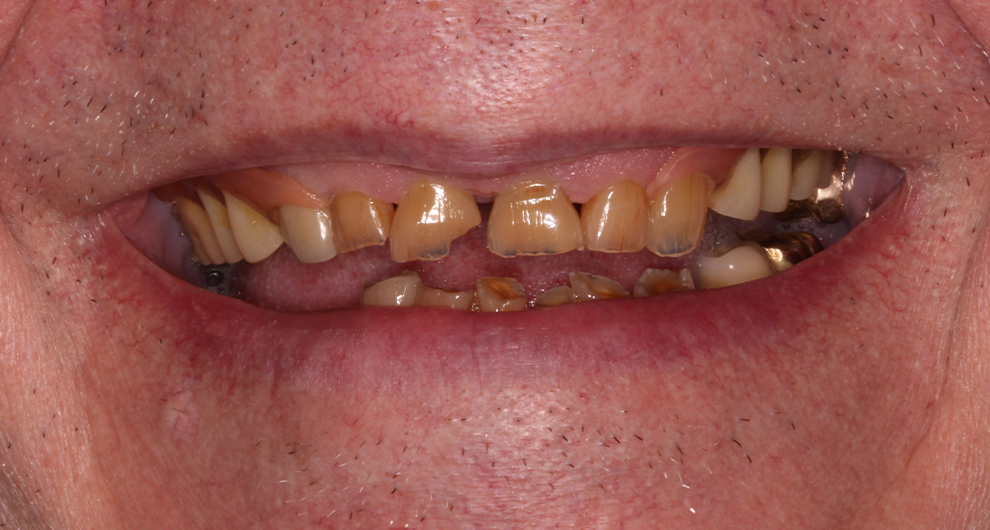

Click and drag the lines to reveal before and after

Before treatment After treatment

Before treatment

After treatment